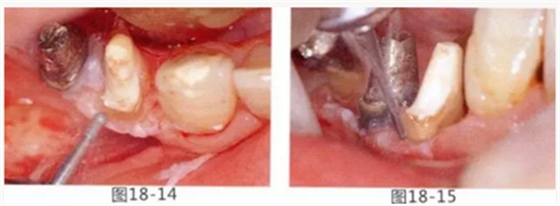

圖18-14 使用圓頭金剛車針進行骨外科處理。

圖18-15 使用鎢鋼車針去除殘留在牙根面的纖維。